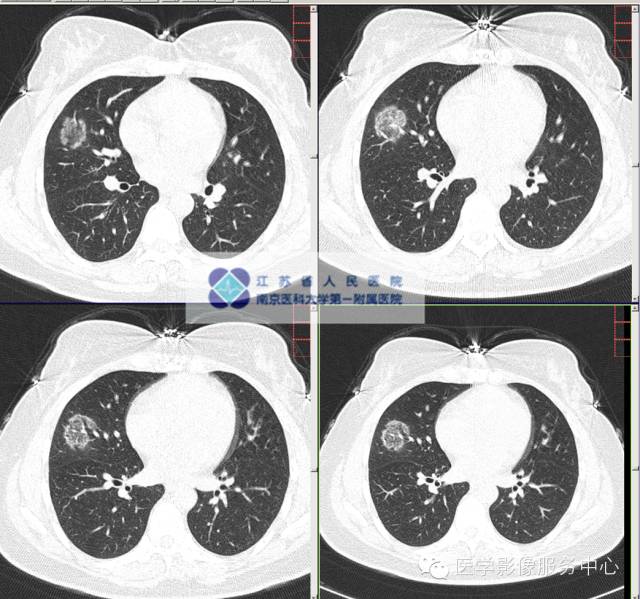

影像分析:右中肺团片状磨玻璃影,境界清晰:纤维组织增生?原位肿瘤?其他?

肺隐球菌病(pulmonary cryptococcosis,PC)是一种侵袭性肺部真菌疾病,主要由新生隐球菌或格特隐球菌引起。PC的临床症状多样,影像改变形态各异,主要表现为结节肿块型、浸润实变型、弥漫性粟粒型及弥漫混合病变型,其中以结节肿块型最为多见,可达57%~82%。以男性群体多见,常发于中青年群体。病灶分布以双下肺外带及胸膜下为主。

结节和肿块性病灶均伴随多种CT征象:

1、晕征、近端支气管充气征对PC的诊断具有特征。

“晕征”表现为病灶周围环绕磨玻璃样密度增高影,为周围炎性渗出所致。

“细支气管充气征” 指在病变的肺组织内仍见透亮的细支气管影,可见于恶性肿瘤或炎症等。CT表现为病变的肺叶中可见扩张、扭曲变形或截断的细支气管,分支稀少。